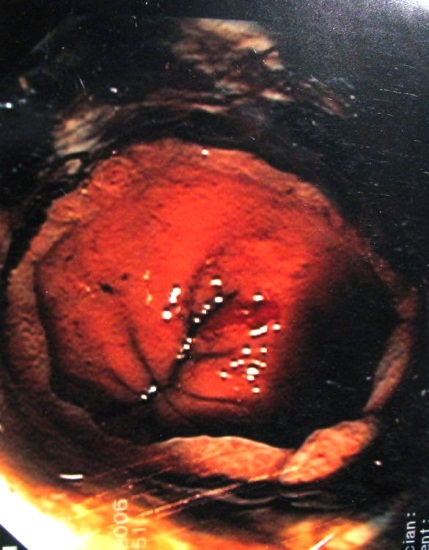

- באנדוסקופיה, המתבצעת לאחר כ-12 שעות, אפשר להעריך את גובה תחילת הפגיעה ואת חומרתה. האנדוסקופיה נועדה לקבוע אם ניזוק הוושט אם לאו. אם יש פגיעה קשה, חייבים להפסיק את האנדוסקופיה עקב החשש לגרימת נקב בוושט על-ידי המכשיר. בילדים יש לבצע את הבדיקה בהרדמה. הנזק המתברר באנדוסקופיה נחלק ל-3 דרגות:

- היפרמיה של הרירית וגודש

- הופעת דימומים, התכייבויות ותפליט (אקסודט - פסוידו-ממברנות) מוגבלות

- קילוף הרירית, דימומים ניכרים עד קשים, כיבים עמוקים, חסימות הנהור ופרפורציות (איור 20.1 - 21.1)